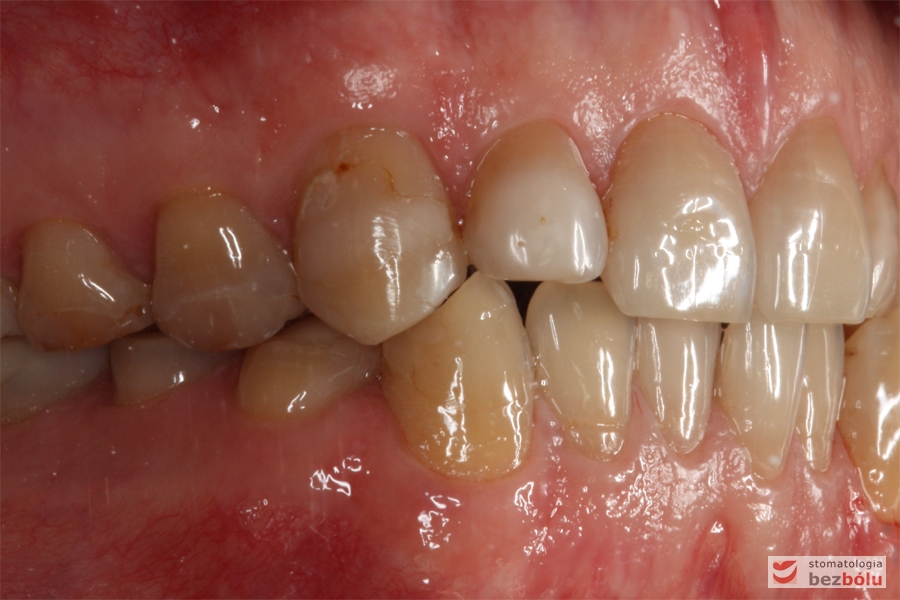

Zęby w zwarciu - strona prawa, przebarwienia świadczące o chorobie szkliwa (hypoplazja)

Zęby w zwarciu – strona prawa, przebarwienia świadczące o chorobie szkliwa (hypoplazja)